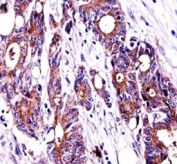

NPM1 antibody immunohistochemistry analysis in formalin fixed and paraffin embedded human colon carcinoma.